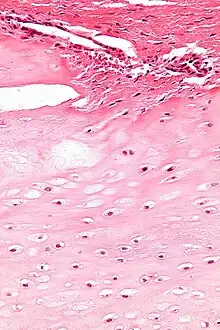

| Enchondromas are present in Maffucci syndrome | |

Maffucci syndrome is a very rare disorder in which multiple benign tumors of cartilage develop within the bones (such tumors are known as enchondromas).[1] The tumors most commonly appear in the bones of the hands, feet, and limbs, causing bone deformities and short limbs.[1]

The enchondromas affect the extremities and their distribution is asymmetrical. The most common sites of enchondromas are the metacarpal bones and phalanges of the hands. The feet are less commonly affected.[4] Disfigurations of the extremities are a result. Pathological fractures can arise in affected metaphyses and diaphyses of the long bones and are common (26%).